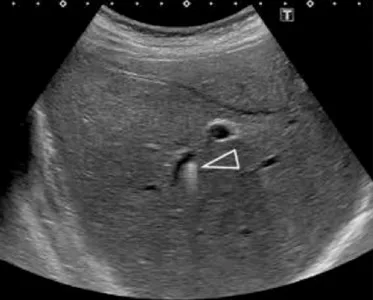

A

B

Figure 10.

A. Mise en évidence de lithiases intrahépatiques en bili-IRM.

B. L’échographie est un complément utile, car la bili-IRM peut avoir du mal à détecter les calculs quand les voies biliaires sont

de petit calibre. Ici l’échographie montre la présence de dépôts de cholestérol le long de petites voies biliaires intrahépatiques, visibles

sous la forme d’une image en « queue de comète », classique mais dont la recherche nécessite une exploration ciblée attentive. Devant des antécédents de cholestase gravidique et de symptomatologie biliaire avant 40 ans ayant récidivé après cholécystectomie, cette patiente présente avec l’imagerie tous les critères diagnostiques d’un syndrome LPAC. Cette prédisposition à la pathologie biliaire pourra être confirmée par une recherche génétique, et donner lieu à un traitement médical et un dépistage familial